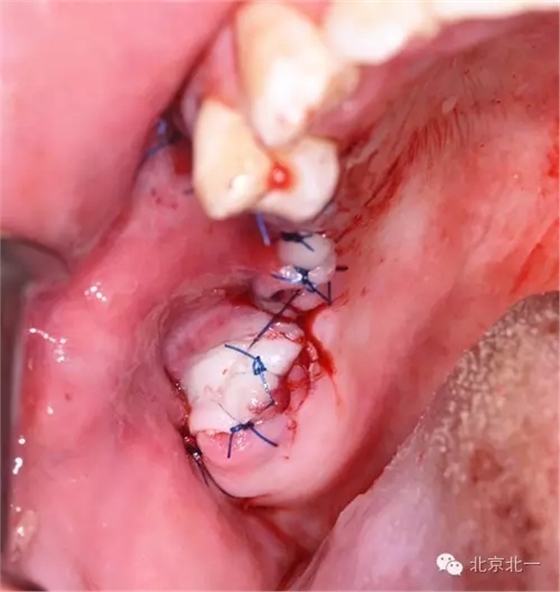

圖一:手術前臨床照片

圖十:縫合。

圖十七:縫合。非潛入